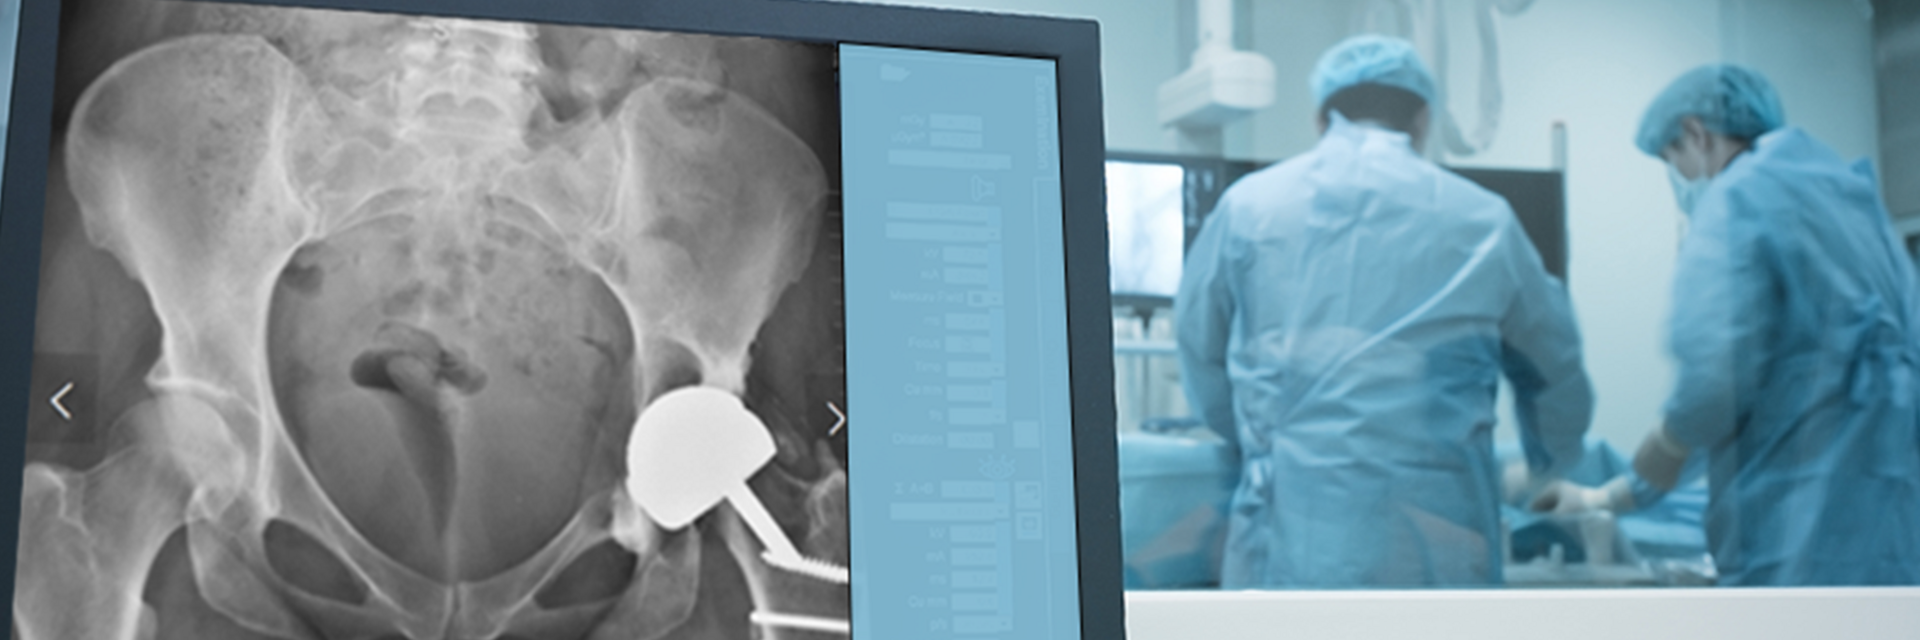

The patient, a 49-year-old woman, underwent metal-on-metal (MoM) hip resurfacing procedure in 2001 due to a unilateral hip dysplasia (DDH). 17 years later, she presented with mild hip pain but extensive loss of bone in the pelvis which was presumably caused by an inflammatory reaction to metal wear debris. Her blood metal ion levels were 100 times higher (cobalt 188 bbp and chromium 126 bbp) than from patients with well-functioning MoM hips.

The case posed multiple challenges. The patient was at imminent risk of pelvic fracture without surgery. However, surgery itself also risked fracture of the pelvis during implant removal. Furthermore, the remaining pelvic bone was poisoned by metal debris and thus the patient’s bone integrity was compromised, which could affect the stability of a new implant.

A multidisciplinary team decided that revision surgery was necessary due to the risk of fracture and very high metal ion levels. The plan involved removing the existing MoM implant and fitting a custom 3D-printed acetabular cup. The procedure required meticulous care to avoid causing fractures during implant removal. The new cup would only be effective if the pelvis remained intact.

The operation was successful, with minimal bone loss during implant removal. A custom-made titanium acetabular cup was fitted and stabilized with screws. Postoperative imaging confirmed correct implant positioning and satisfactory fixation. The patient’s recovery was positive, with significant reductions in metal ion levels and the restoration of pain-free hip function.

This case represents ALTR with MoM, which was characterized by extensive osteolysis of pelvic bone, which was presumably caused by metal wear debris. Elevated blood levels of chromium and cobalt further supported this hypothesis.